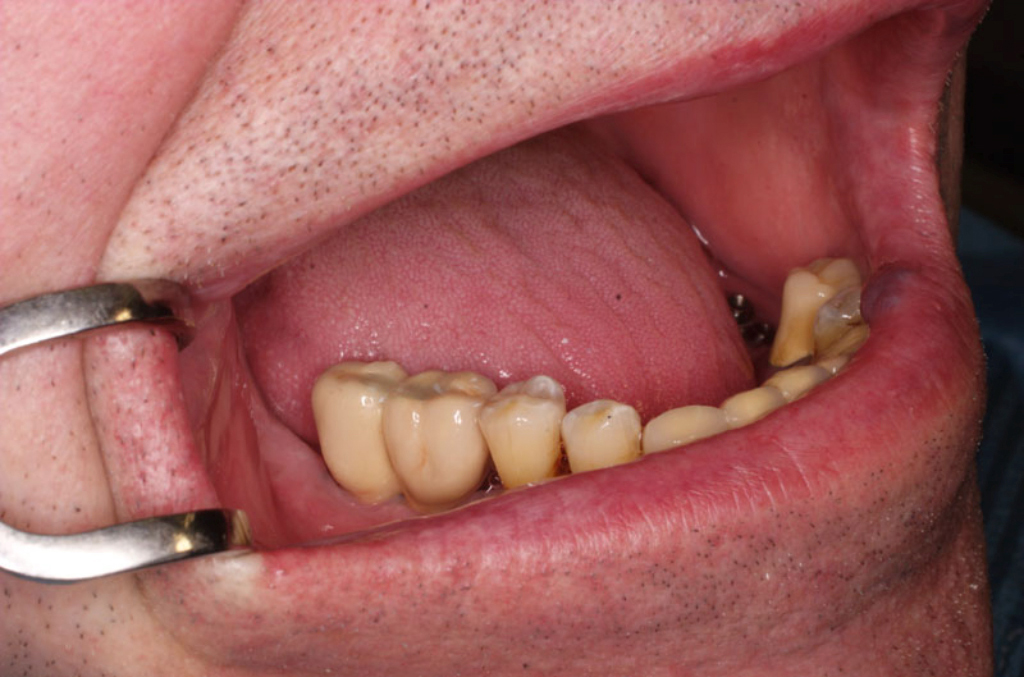

Během let může postupnou ztrátou zubů zůstat v ústech omezený počet zubů, které umožňují držení zubních náhrad.

V důsledku přetížení zbylých zubů např. houpavými pohyb snímacích náhrad dochází k uvolnění těchto zubů a držení můstků a protéz je tak velmi těžké. V těchto případech můžeme pomocí implantátů zvýšit počet pilířů a tím zabránit přetěžování a ztrátě zbylých zubů